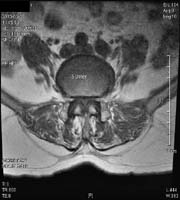

<ôÃß°ÇùÂøÁõ>

¾çÃø

ÇÏÁö ¹æ»çÅë°ú °£ÇæÀû ÆÄÇàÀ» ÁÖ¼Ò·Î ³»¿øÇÑ

ȯÀÚÀÇ ¿äÃߺΠMRI ¼Ò°ßÀ¸·Î ôÃß°ü ÇùÂøÀ¸·Î

ÀÎÇØ ô¼ö½Å°æÀÌ ¾Ð¹Ú ¹Þ´Â ¼Ò°ßÀ» º¼

¼ö ÀÖ´Ù.